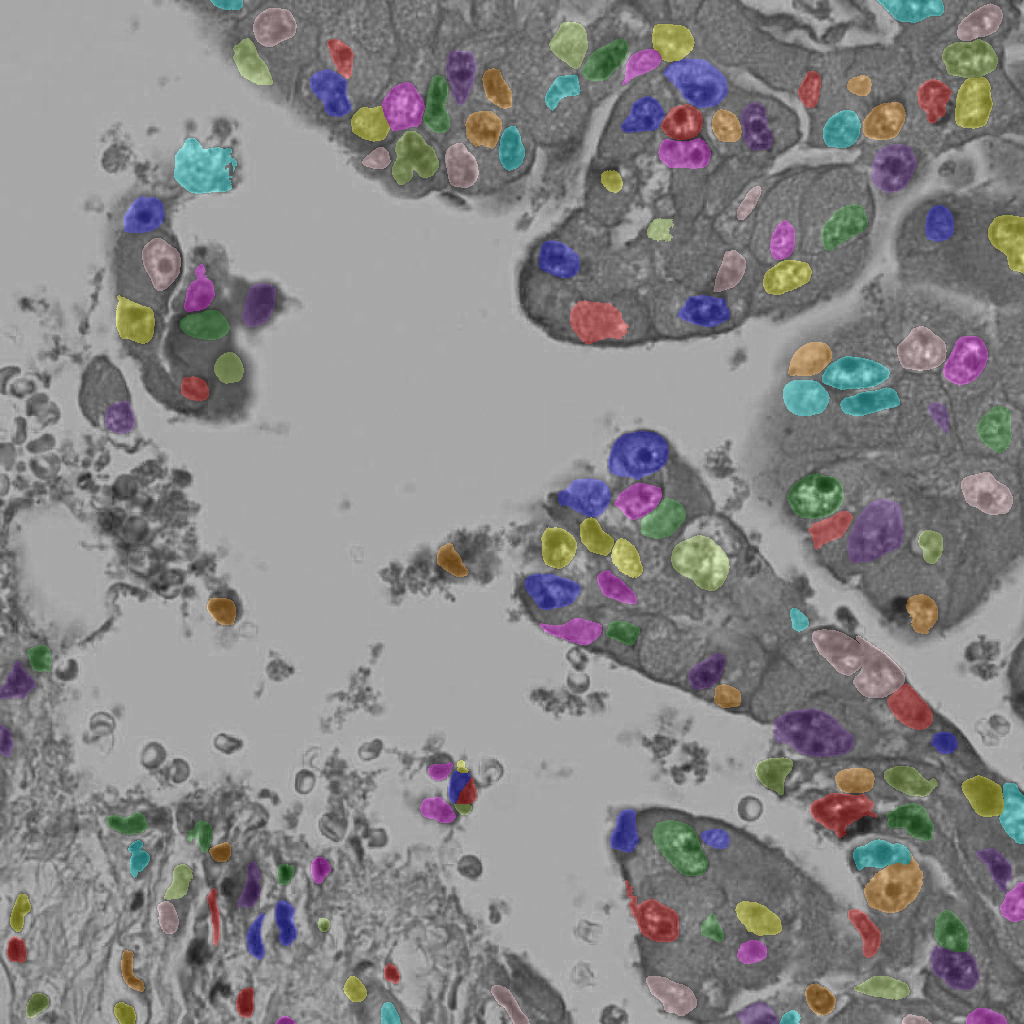

Appendix 0.A Segmentation ground truth generation with NuClick

We utilize NuClick [1], a pretrained nucleus, cell and gland segmentation model444Publicly available at https://github.com/navidstuv/NuClick, last accessed 24.11.2023, to extend the cell annotations from centroid coordinates to segmentation maps, as visualized in Figure 5. It relies on a guiding signal, in our case the cell point annotations, together with the input image for instance segmentation. Pretrained weights are only available for nuclei segmentation555https://drive.google.com/file/d/1MGjZs_-2Xo1W9NZqbq_5XLP-VbIo-ltA/view, last accessed: 24.11.2023, for this reason we extend the ground truth to a nuclei segmentation mask instead of a cell segmentation mask.